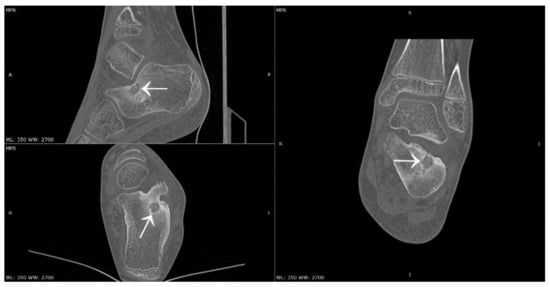

3.4. Case 4: OO Masking as a Fatigue Fracture

- Wałejko, S.; Mazurek, T.; Żychliński, M. Bifocal osteoid osteoma of the talus treated with thermal ablation and navigation 3D—Case report. Chir. Narz. Ruchu Ortop. Pol. 2020, 85, 25–28. [Google Scholar] [CrossRef]